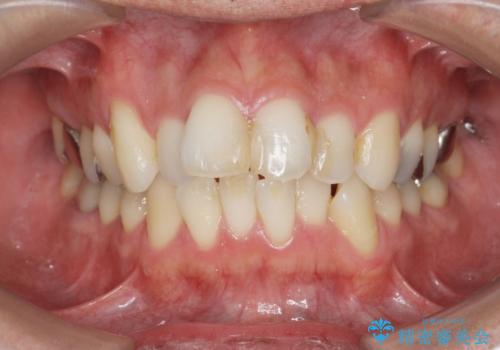

[セラミック治療] 前歯の審美治療に伴う矯正治療